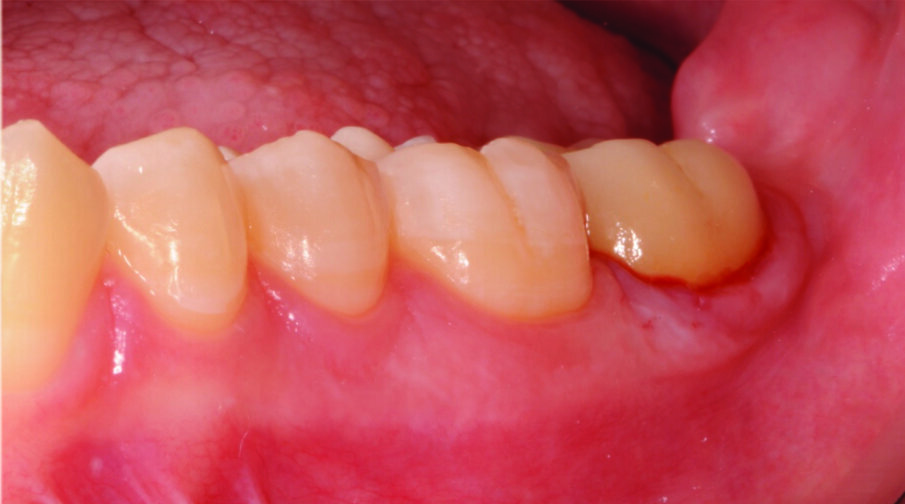

Fig. 1: Initial Situation with a molar tooth in need of endodontic treatment and subsequent crown placement.